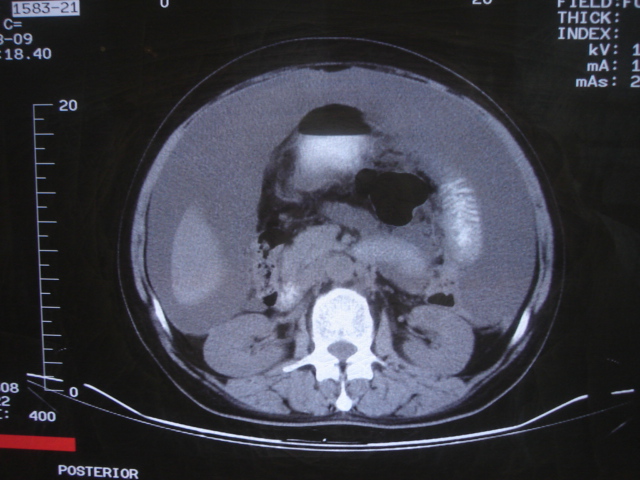

患者 女 52 腹部大量腹水。大家帮忙看看胃窦部有问题吗?

b超显示腹部、盆腔未见异常;化验室检查afp cea 正常,ca125 升高 347.4。

腹部大量腹水。胃窦部胃壁增厚,轮廓不规则!

1)不排除胃癌可能;建议行胃镜检查。2)大量腹水。

网膜不干净,可能为癌性腹膜炎。

腹部大量腹水。胃窦部胃壁增厚,轮廓不规则,胃癌待除外,建议胃镜检查。